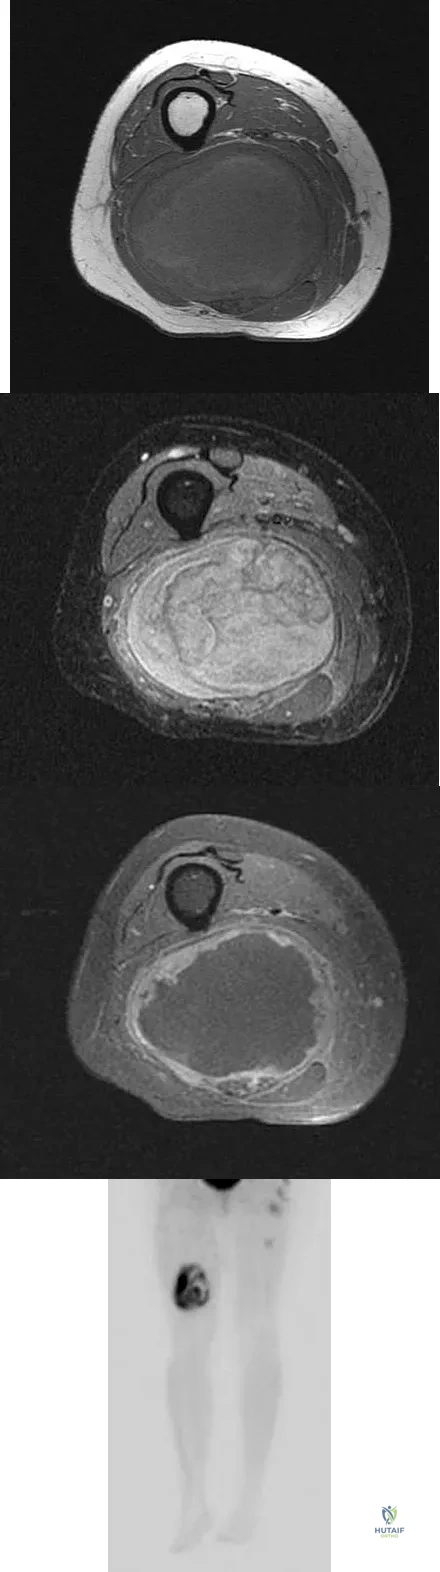

A 36-year-old woman with familial neurofibromatosis has an enlarging mass in the posterior thigh. The lesion has slowly increased in size and is now constantly painful. Pressure on the mass causes dysesthesias in the foot. Figures 44a through 44c show T1-weighted, STIR, and T1-weighted fat-saturated gadolinium scans, respectively. Figure 44d shows a PET scan. What does this lesion most likely represent?

Explanation